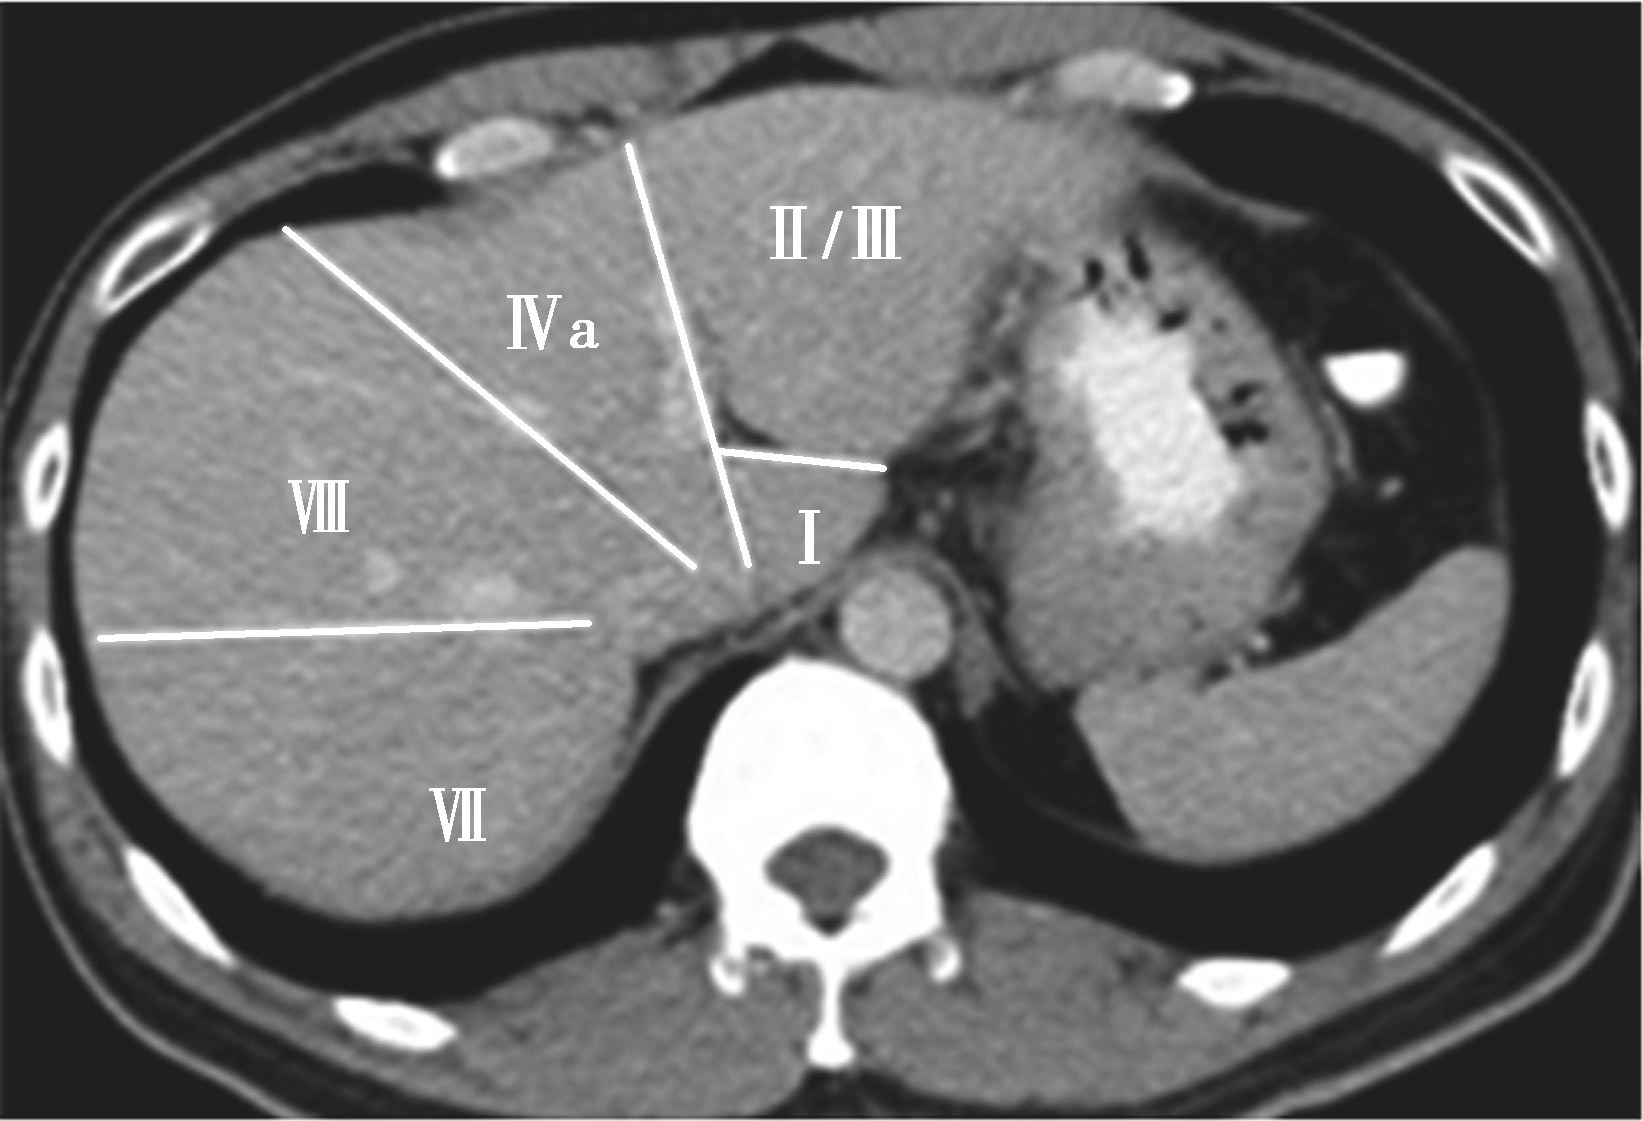

(3)肝8段划分法(图5-21-35):

Couinaud根据门静脉及肝静脉的分布将肝脏分为8段,门静脉分布于肝段内,肝静脉分布于肝段间。8分段法是临床外科和影像最为常用的分段法。以肝中静脉为界分为左、右半肝;以肝左静脉为界将左半肝分为左内(Ⅳ段)和左外叶(Ⅱ段+Ⅲ段);左外叶以门静脉左支为界水平分为上(Ⅱ段)下(Ⅲ段)两段;以肝右静脉为界分右半肝为前叶(Ⅷ段+Ⅴ段)和后叶(Ⅵ段+Ⅶ段);以门静脉右支为界将右肝横向分为上下两段分别为右前上段(Ⅷ段)、右前下段(Ⅴ段),右后下段(Ⅵ)和右后上段(Ⅶ段);肝尾状叶为单独一段(Ⅰ段)。

图5-21-35 肝8段划分法示意图